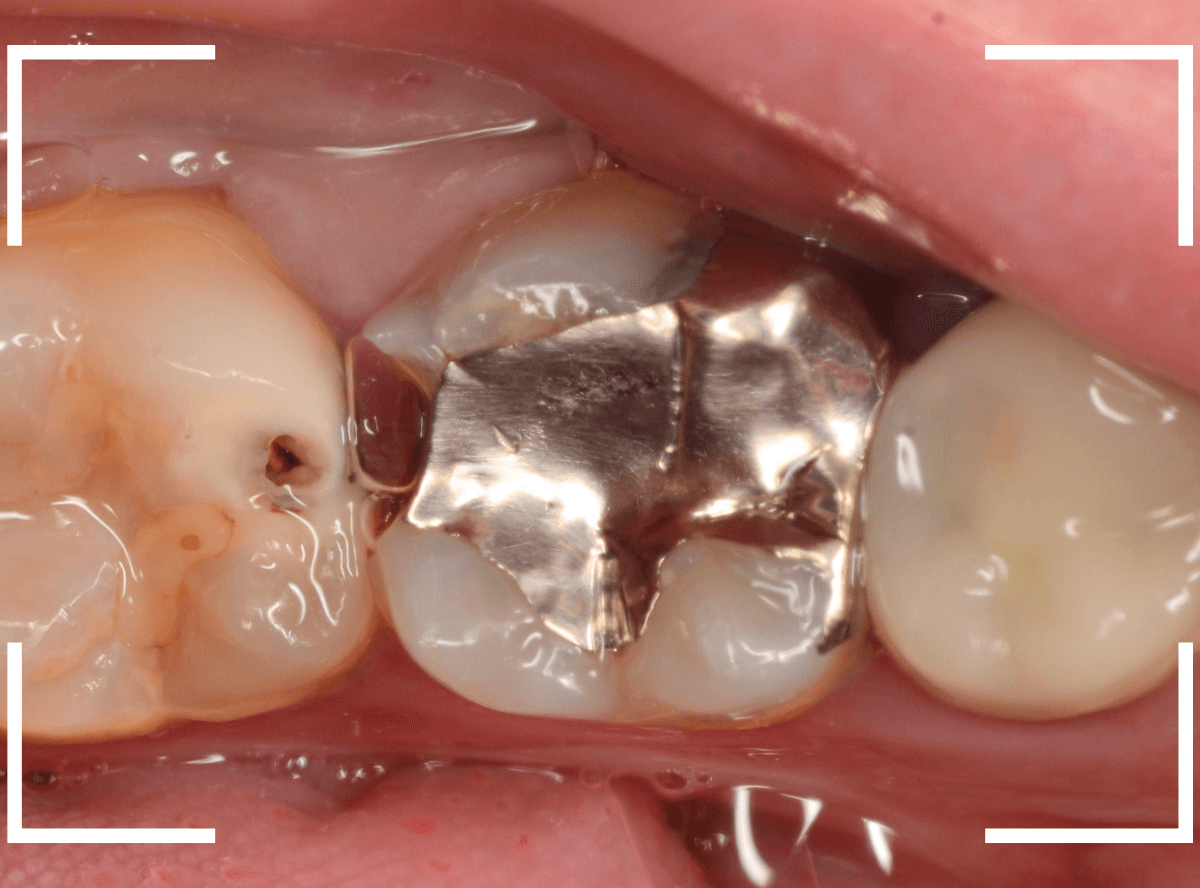

Case.18 2本に渡る大きな虫歯

「歯に大きな穴が開いていて痛い」という訴えで来院された患者さんです。

金属のつめものの脇に大きな穴が開いているのがわかります。

レントゲン写真で確認します。

赤い線が虫歯、青い線が神経です。

奥歯も神経に到達しそうな、大きな虫歯になっているのがわかります。

早めの治療が必要です。

まず、慎重に金属を除去します。

金属の下に敷いてあったセメントも劣化しているのが分かりますので、そちらも除去して調べます。

セメントも除去したところです。

両歯とも、とても大きな虫歯なのがわかります。